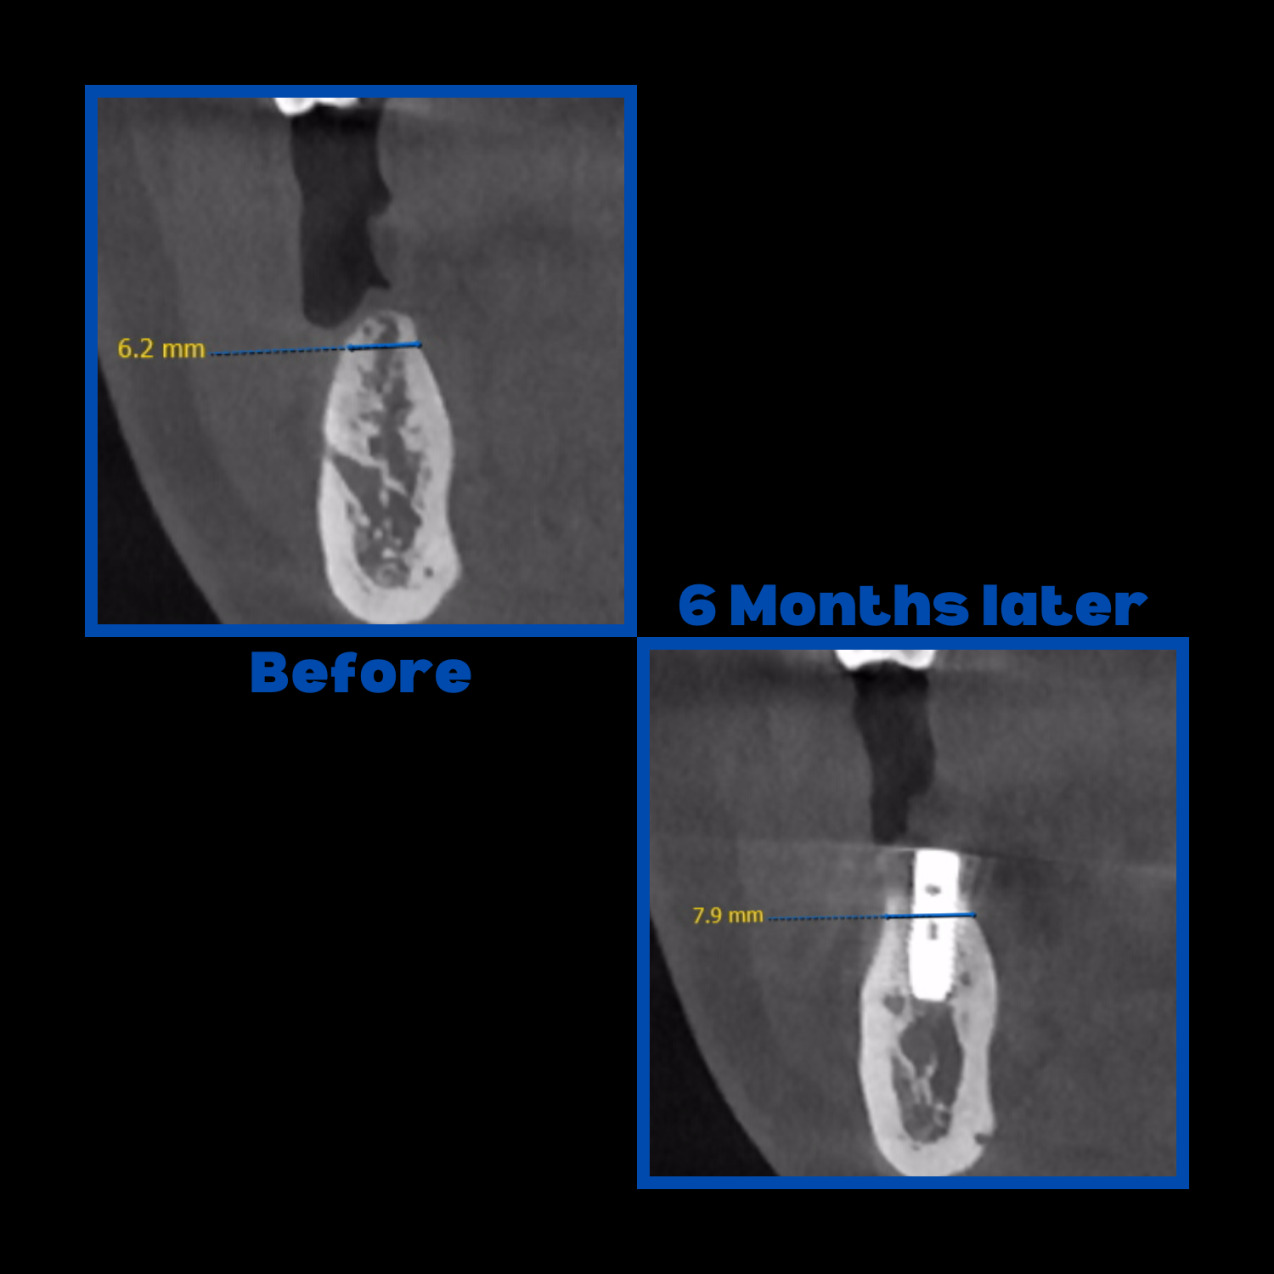

Diş çekiminin yıllar önce yapılmış olmasına bağlı olarak ince kemik varlığında implant ve kemik grefti uygulandı